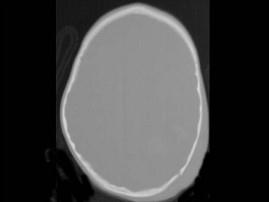

问题 男,3岁,头颅被球击中,请结合CT图像,最选择可能的诊断是 ( )

选项 A、动脉瘤破裂出血 B、血管畸形 C、脑结核 D、脑挫裂伤血肿形成 E、高血压性脑出血

答案 D